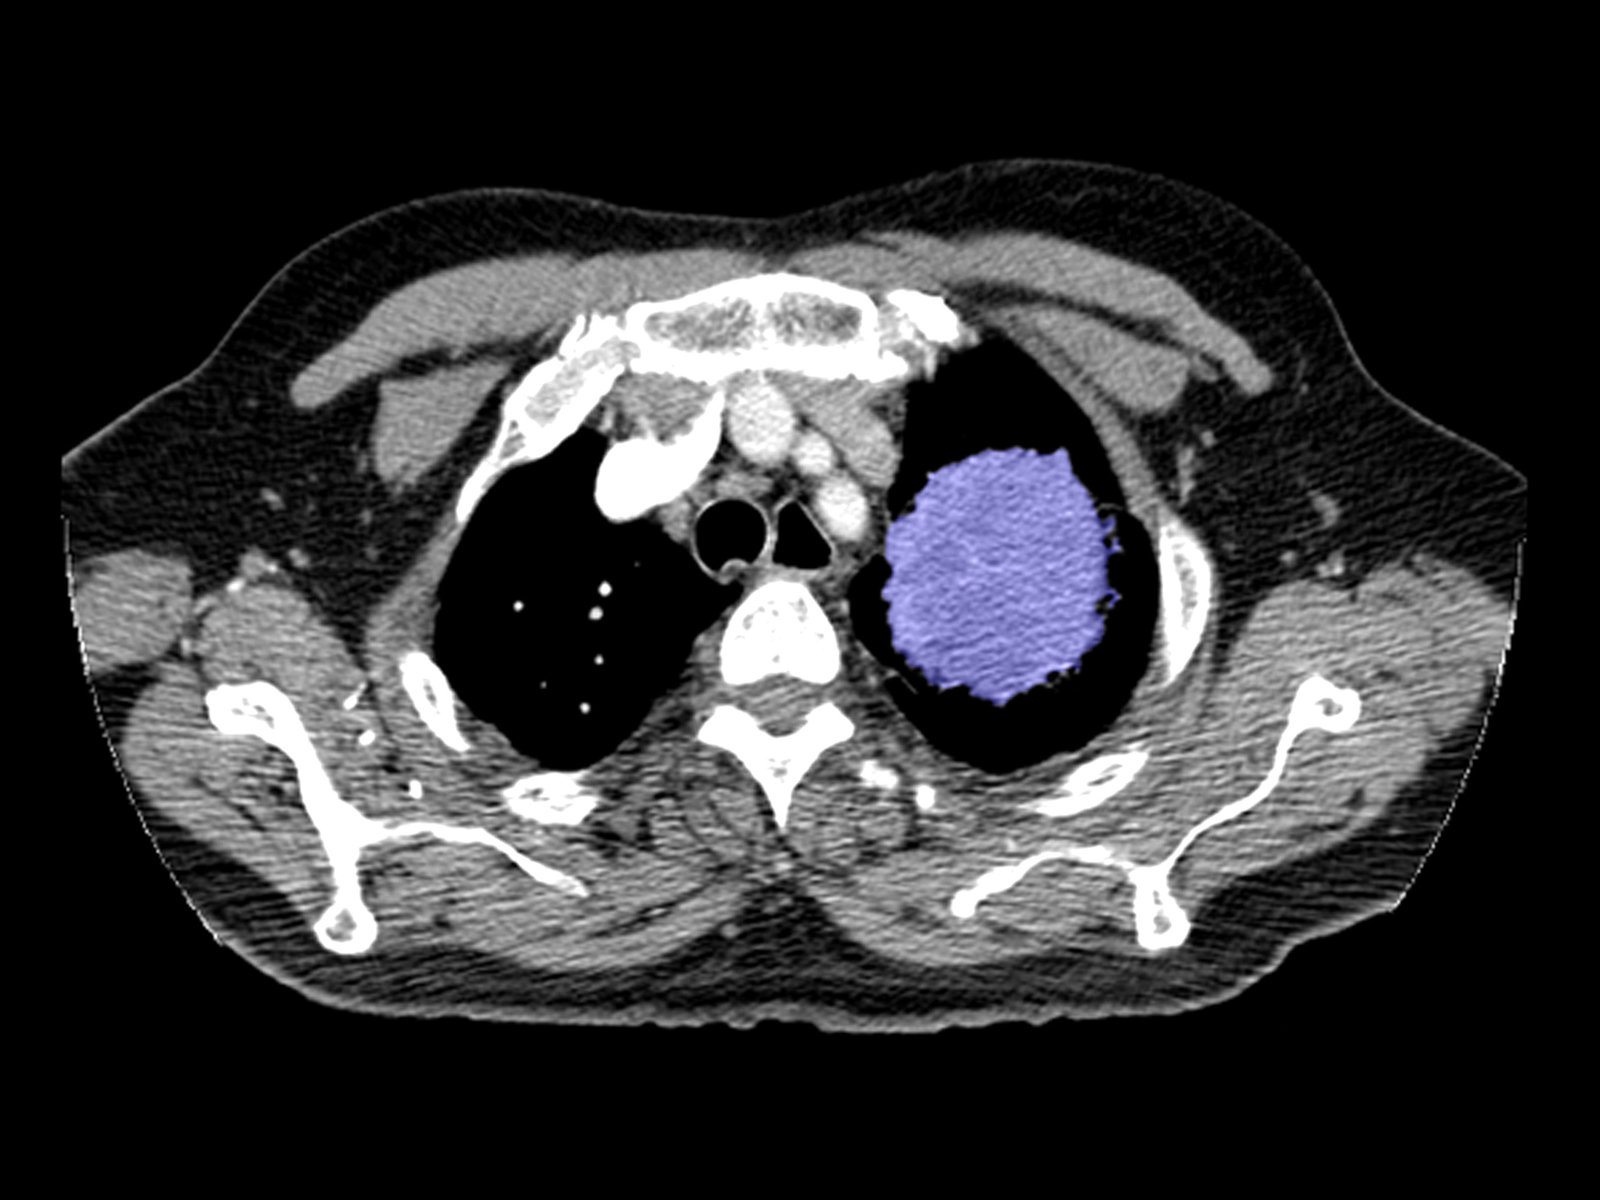

How to Identify a Pulmonary Embolism on CT Search Pattern for CTA

How to Identify a Pulmonary Embolism on CT Search Pattern for CTA How Long Does A Chest Ct Scan Last Computed tomography, more commonly called a cat scan or ct scan, is a diagnostic test that uses a series of. your healthcare team will then lead you to the room with the ct scanner, a large machine with a tunnel in the center,. But for repeated scans, there may be a small increase. what is a ct scan?. How Long Does A Chest Ct Scan Last.